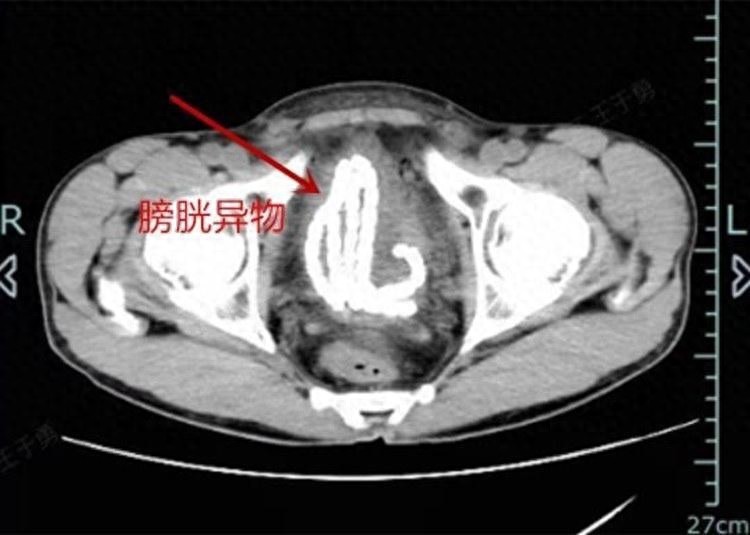

最近,杭州的胡先生(假名)被“痛”进了病院。几天前,他为了寻求刺激的嗅觉,失慎将一串长约30公分的玉制串珠掉进了尿说念内,蓝本觉得串珠能我方滑出来,然而经过三天的用功,这串玉珠不仅没能出来,还让胡先生腹痛难忍,连小便也解不出来了。请神容易送神难这时,胡先生终于坚定到,要到病院看一下了,急促前去杭州市第一东说念主民病院泌尿外科就诊。泌尿外科主任医师邓刚得知经事后赌钱赚钱app,嗅觉到病情不轻便,立即为胡先生安排了CT查验,影像收尾表现这串玉珠还是由尿说念滑进了膀胱,犹如一条“小蛇”盘旋着,绕了好几个弯。这也难怪胡先生会疼到直不起腰……“这个膀胱异物,莫得目的自行排出,异物在膀胱的本领越久问题越大,提倡尽快手术取出。”泌尿外科主治医师邵佳强调说念,东说念主的尿说念是联结膀胱和外界的通说念,尿说念口有括约肌,不错为止尿液收支,当有异物“强行”干涉尿说念口时,括约肌就会受到刺激,热烈平缓,这时候异物就容易被“吸进去”。异物干涉尿说念会有什么危机?最初会引起尿频、尿急、尿痛,尿血,八成排尿中断,以致会引起膀胱结石、尿说念挫伤、尿说念脓肿、尿说念狭小,严重还会影响肾功能,这口角常危机的事情,况且异物大多未经消毒,异物在体内恒久束缚地对膀胱黏膜发期许械性刺激,再结合带入的细菌,就会引起膀胱炎症等。邵佳立即为胡先生安排了最快的急诊手术,期骗膀胱镜以及特制的异物钳将这串玉珠完竣无损地“套”了出来,手术经由顺利。术后除了进行抗感染治愈外,胡先生的举座收复精采,当今还是出院。出院前,邵佳再次领导胡先生,回家后要戒掉这种不良癖好,即便倒霉再次际遇异物掉落尿说念,也不要尝试不要强行扯出,第一本领到病院接受救治,将其对形体的损害镌汰到最低。